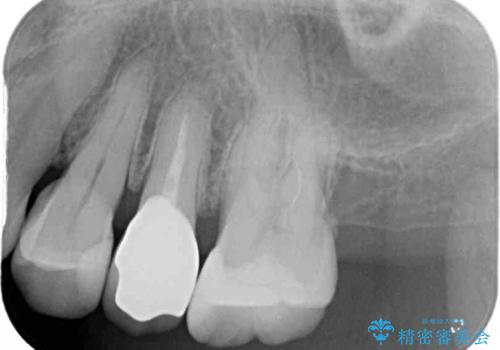

仮歯に変えた後にオールセラミッククラウンにて補綴することとしました。

治療前と比べてとても自然な前歯となり、患者様には大変満足していただきました。